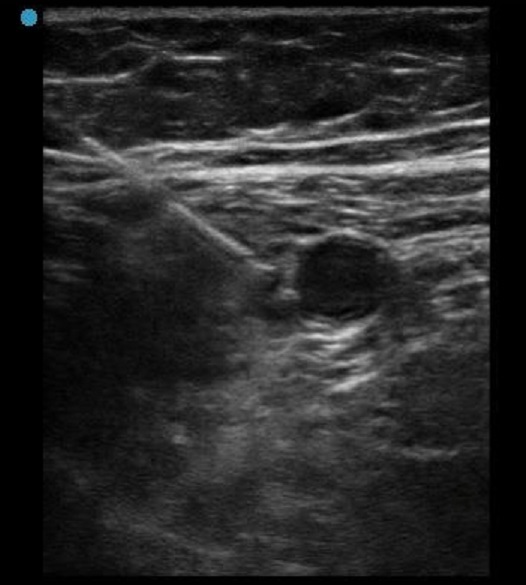

Imagen previa a la inyección infraclavicular